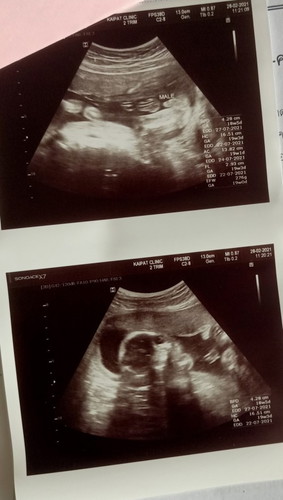

19สัปดาห์1วัน

ตอนนี้ได้19สัปดาห์1วันน้องๆบ้านไหนน้ำหนักเท่าไรกันแล้วค่ะ บ้านนี้276กรัมแล้วค่ะ😊😊